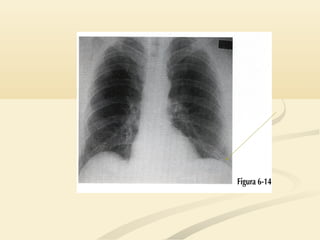

 La consolidación del LSI borrará la aurícula izquierda,La consolidación del LSI borrará la aurícula izquierda,

el botón aórtico y el mediastino anterior y medioel botón aórtico y el mediastino anterior y medio..

 La consolidacióndel LSI borrará la aurícula izquierda,La consolidación del LSI borrará la aurícula izquierda, el botón aórtico y el mediastino anterior y medioel botón aórtico y el mediastino anterior y medio..